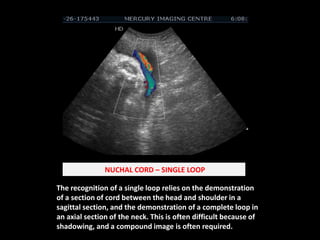

What is a loop of Cord around the neck? | Dr. Sukhamoy Barik ...

Cord-Around-the Neck (Nuchal Cord) - Rivin | PPTX

Umbilical Cord Around Neck Ultrasound Nuchal Cord An Overview

How to see Single Loop Around the Neck.|| By: Dr. Nabin|| #india # ...

Cord around the_neck. | PPTX